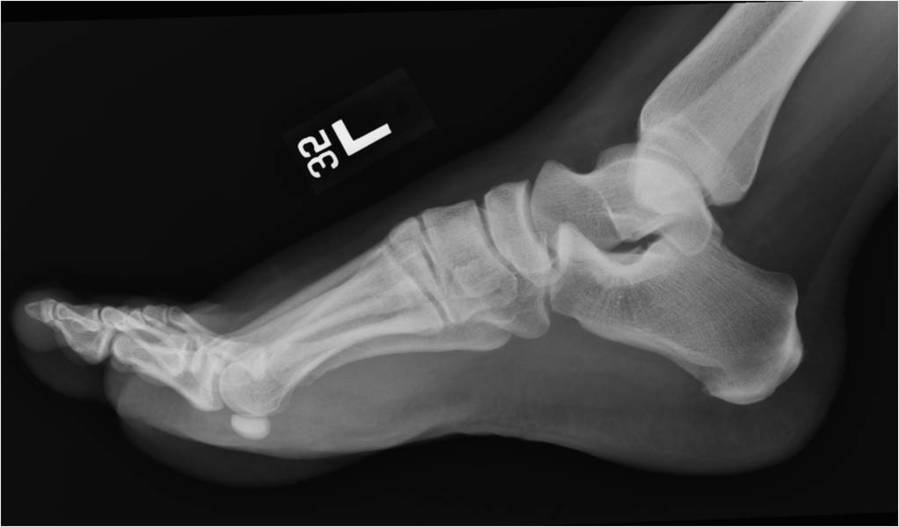

Gallery of Unlabled Radiographs from Lecture (Dr. French) - 2020

Click a thumbnail to enter the gallery display. Click the file name link at the bottom left of the gallery display to view the image at high resolution.

Labeled Plates from Lecture (Dr. French) - 2020

RadiologyLowerLimbThoraxQuestionPoolLabeled_01_2020.pdf

Click right side of plate to step forward or left side of plate to step backward.